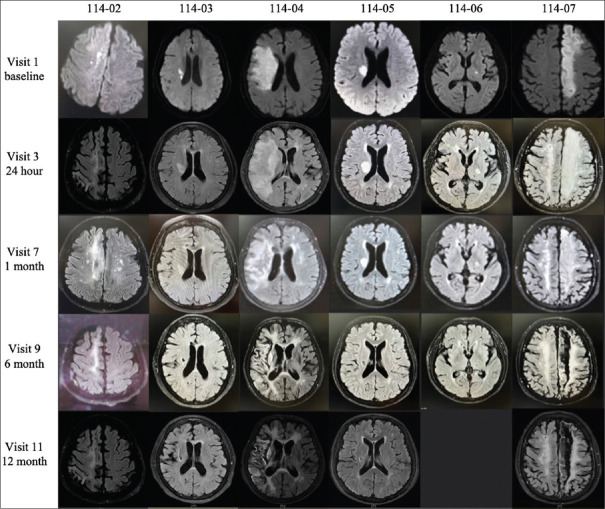

Materials and methods: We conducted a 12-month, open-label, and single-center, phase I trial of hUCB treatment in AIS patients at the age of 45-80 years, with magnetic resonance imaging evidence of acute infarction in the internal carotid artery supplied territory and the National Institute of Health Stroke Scale (NIHSS) score between 6 and 18. Eligible participants received a single-dose IV infusion of hUCB followed by the two doses of mannitol infusion within 9 days after the onset of stroke symptoms. The primary endpoint was the incidence of adverse events (AEs) and the secondary endpoints were the changes in NIHSS, Barthel index (BI), and Berg Balance Scale (BBS) scores.

Results: Six patients (Male: Female = 3: 3) were enrolled with a mean age at 65.8 years. A total of 40 AEs occurred in six participants during this study, which included nine serious adverse events. Only transient erythema multiforme and hematuria were probably and possibly related to hUCB infusion, respectively. The mean NIHSS score was 11.5 at baseline and it significantly improved at 1, 3, 6, 9, and 12 months after treatment (mean change from baseline: -4.0, -5.3, -6.8, -7.0, and -7.3). The mean BI score was 22.5 at baseline and it significantly increased at 3 and 6 months after treatment (mean change from baseline: 26.7 and 42.5, respectively). The BBS score increased numerically but did not reach statistical significance. The changes in cytokine levels and spleen size were unremarkable.